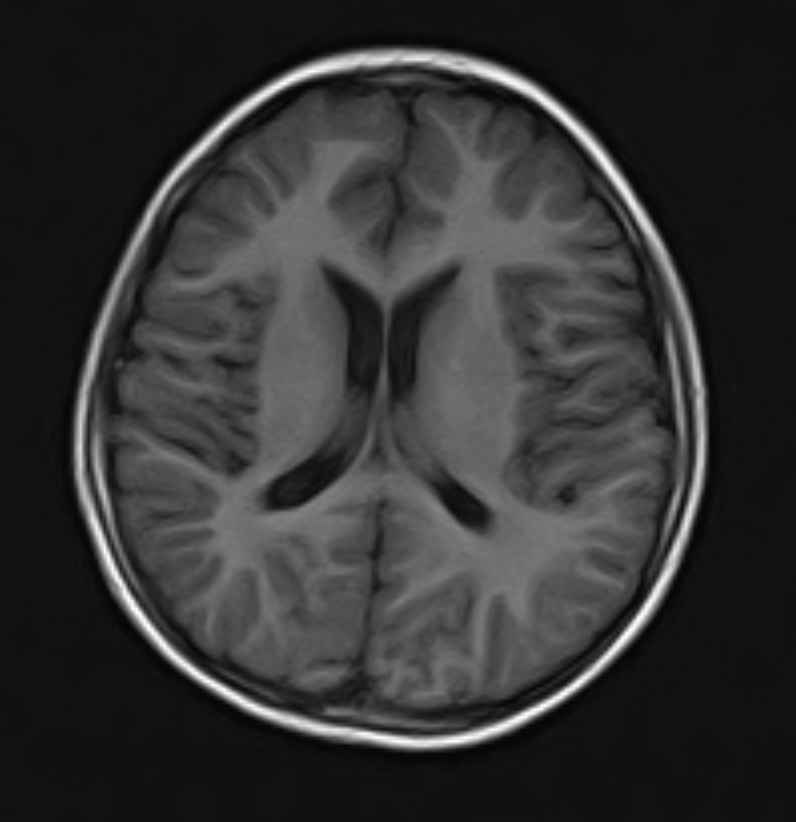

Neurological Disorders | Acute intracranial hemorrhage, skull fractures, ischemic stroke (acute phase) | Brain tumors, demyelinating diseases (e.g., multiple sclerosis), epilepsy focus localization, spinal cord pathologies |

Spine | Spinal fractures, spinal instability, bone lesions | Spinal cord tumors, disc herniation, nerve root compression, inflammatory conditions |